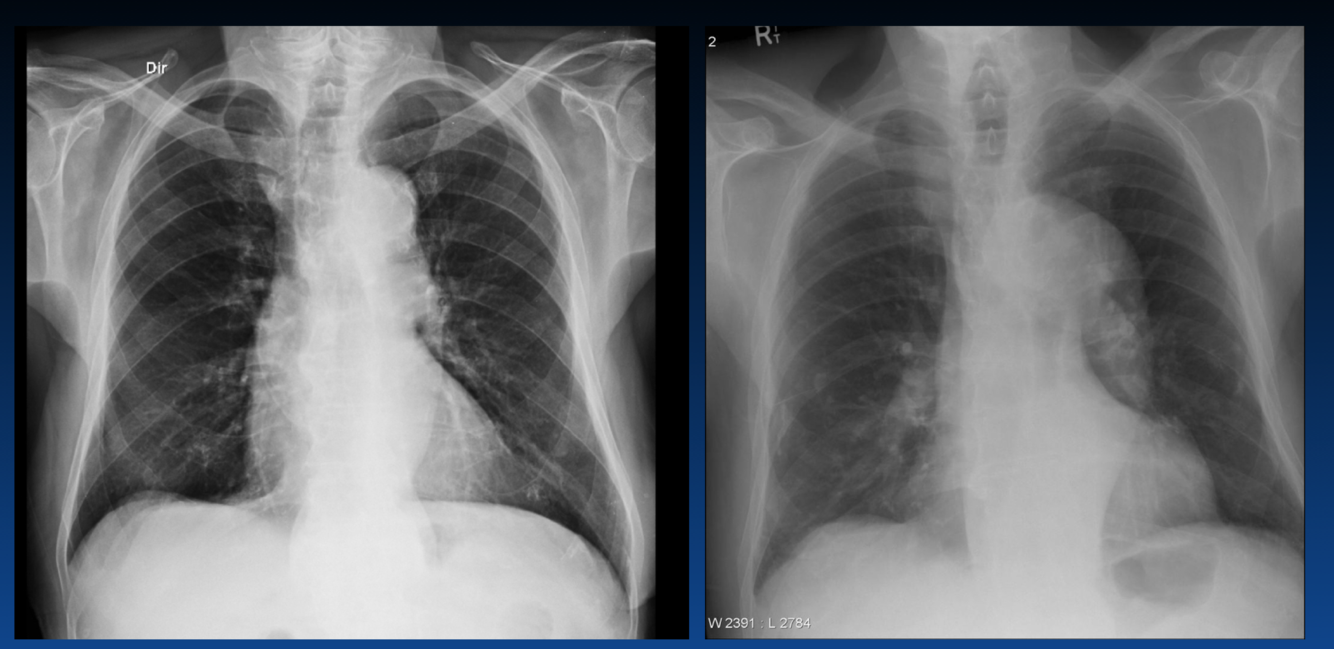

Is this aortic regurgitation or aortic stenosis?

How can you tell the difference between aortic regurgitation and aortic stenosis on an x-ray?

Regurge is wider